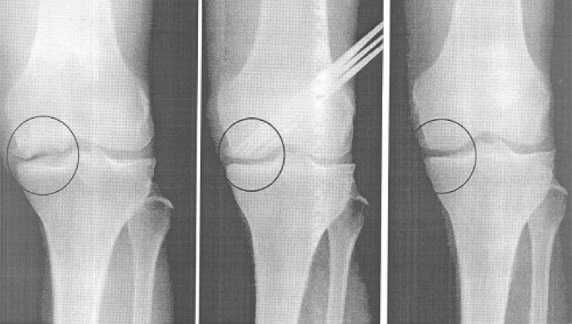

2) Стандартная рентгенография:

1. Задне-передняя проекция в положении стоя при сгибании коленных суставов до 45°: диагностика в первую очередь патологии заднего отдела тибиофеморального сочленения, остеофитов в этом отделе сустава, уплощения и заострения краев мыщелков бедра

2. Рентгенография в прямой и боковой проекциях: подвывих большеберцовой кости, задние остеофиты мыщелков бедра:

• Рентгенография должна проводиться с использованием маркеров заданного размера, позволяющих оценить масштаб рентгеновского изображения и вычислить точные размеры необходимого трансплантата мениска

• Ширина мениска измеряется по рентгенограмме в прямой проекции от края одноименного бугорка большеберцовой кости до края ее плато

• Длина мениска измеряется по рентгенограмме в боковой проекции как расстояние от линии, параллельной передней поверхности большеберцовой кости, до линии, перпендикулярной заднему краю плато, и умножения полученного значения на 0,7 (для наружного мениска) или 0,8 (для внутреннего мениска) с поправкой на увеличение рентгеновского изображения